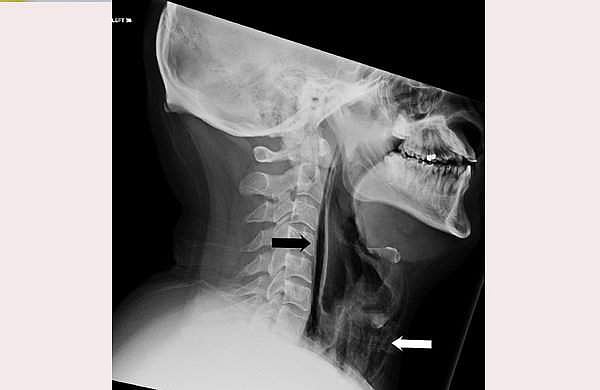

ബിഎംജെ കേസ് റിപ്പോര്‍ട്ട്‌സ് എക്‌സില്‍ പങ്കുവെച്ച ചിത്രം

ലണ്ടന്‍: തുമ്മല്‍ പുറത്തേയ്ക്ക് വരുന്നത് തടയാന്‍ വായും മൂക്കും അടച്ചുപിടിച്ച ബ്രിട്ടീഷ് പൗരന്റെ തൊണ്ടയ്ക്ക് പരിക്ക്. തുമ്മല്‍ അടക്കിപ്പിടിക്കാന്‍ ശ്രമിക്കുന്നതിനിടെ, തുമ്മലിന്റെ ശക്തി കാരണം 34കാരന്റെ തൊണ്ട പൊട്ടാന്‍ കാരണമായതായി ബിഎംജി കേസ് റിപ്പോര്‍ട്ടിലെ പ്രബന്ധത്തില്‍ പറയുന്നു.

ഭക്ഷണം കഴിക്കുമ്പോള്‍ വേദന അനുഭവപ്പെടുക, ശബ്ദത്തില്‍ മാറ്റം, കഴുത്തില്‍ നീര് തുടങ്ങിയ ലക്ഷണങ്ങള്‍ കണ്ടതിനെ തുടര്‍ന്ന് യുവാവ് ചികിത്സ തേടിയതോടെയാണ് തൊണ്ട പൊട്ടിയ കാര്യം കണ്ടെത്തിയത്. തുമ്മല്‍ അടക്കിപ്പിടിക്കാന്‍ ശ്രമിക്കുന്നതിനിടെ, തൊണ്ടയിലെ ചില കോശങ്ങളില്‍ വായു കുടുങ്ങിയതിനെ തുടര്‍ന്നാണ് തൊണ്ട പൊട്ടിയതെന്ന് ഡോക്ടര്‍മാര്‍ പറഞ്ഞു. ശ്വാസനാളത്തിന്റെ സ്വമേധയാ ഉള്ള വിള്ളല്‍ വളരെ അപൂര്‍വമാണ്. സാധാരണയായി ഛര്‍ദ്ദി, വേദന, കനത്ത ചുമ അല്ലെങ്കില്‍ ഏതെങ്കിലും തരത്തിലുള്ള ആഘാതം എന്നിവ മൂലമാണ് ഇത് സംഭവിക്കുന്നത്.

കഴുത്തില്‍ കടുത്ത അണുബാധ ഉണ്ടാവാതിരിക്കാന്‍ യുവാവിനെ ആശുപത്രിയില്‍ നിരീക്ഷണത്തിലാക്കി. ആന്റിബയോട്ടിക്‌സ് അടക്കമുള്ള ചികിത്സാരീതികള്‍ വഴി രണ്ടാഴ്ച കൊണ്ട് തന്നെ യുവാവിന്റെ രോഗം ഭേദമായതായും ഡോക്ടര്‍മാര്‍ പറയുന്നു. തുമ്മല്‍ വരുമ്പോള്‍ ഇത്തരത്തില്‍ അടക്കിപ്പിടിക്കാന്‍ ശ്രമിക്കുന്നത് ആരോഗ്യത്തിന് ഹാനികരമാണെന്നും ഡോക്ടര്‍മാര്‍ മുന്നറിയിപ്പ് നല്‍കി.